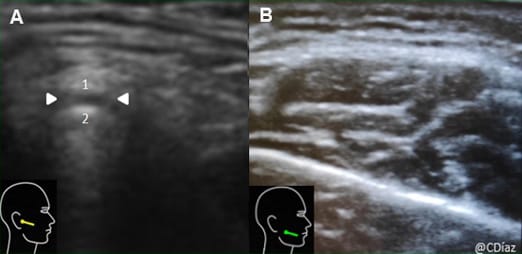

Échographie Échographie des voies aéro-digestives : peut-elle améliorer le suivi des patients en rééducation de la déglutition ? À propos d'un cas clinique